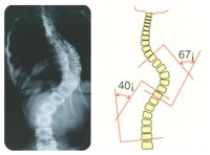

Основными диагностическими инструментами являются история болезни, физический осмотр и рентген. Рентгеновский снимок позволяет измерить степень кривизны позвоночника и определить оптимальное лечение. В случае атипичного или врожденного сколиоза рекомендуются дополнительные процедуры визуализации (КТ, МРТ).

При сколиозе выделяют четыре степени заболевания:

Первая степень. Первая степень сколиоза – это минимальное искривление позвоночника, когда он отклонен от оси менее, чем на 10 градусов. На данной стадии обнаружить заболевание может только врач при специальном осмотре, так как никаких болей в позвоночнике у пациента не возникает, а асимметрия еще не достигла заметной степени. Первая степень сколиоза хорошо поддается лечению, позвоночник можно полностью исправить до здорового состояния.

Вторая степень. При второй степени угол наклона от оси составляет 11-25 градусов. Это уже более серьезная стадия заболевания, при которой необходимо срочно начинать лечение, потому что если болезнь будет прогрессировать, справиться с ней уже будет гораздо сложнее. Первая и вторая степени сколиоза хорошо поддаются лечению, однако после перехода болезни в третью стадию полностью справиться с ней уже практически невозможно.

Третья и четвертая степени. Это последние стадии заболевания, при которых позвоночник отклонен от оси от 25 градусов и более. Полное выпрямление позвоночника при этом уже не является возможным, поэтому основной задачей врача становится уменьшение симптоматики.

Основным методом диагностики сколиоза в клиниках Турции является рентгенография. Снимок проводится в прямой проекции, это позволяет выявить боковые смещения позвоночника. На основе данных рентгенографии проводится оценка степени сколиоза, это позволяет врачу выбирать дальнейшую тактику лечения.

Частой формой сколиоза является юношеская форма идиопатического сколиоза. В случае, если искривление позвоночника в самом начале выявления невыраженное, можно обойтись простым наблюдением и периодическим проведением рентгенографии. При этом, если угол искривления позвоночника менее 25 градусов, другого лечения не требуется. При значении угла искривления 25 – 40 градусов, может потребоваться фиксация позвоночника. Если угол искривления более 40 градусов, то применяется оперативное вмешательство.